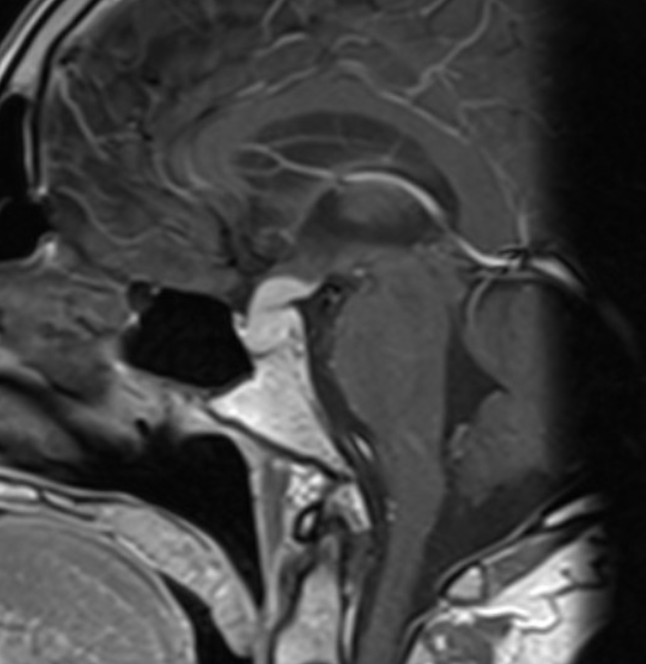

CT and MRI

Both CT and MRI can be used to delineate the malformation cross-sectionally.

MR angiography

The dilated feeding and draining vessels appear as flow-voids on T2. MRA may also be performed which would better delineate vascular anatomy.

Angiography

Angiography remains the gold standard in full characterisation of the lesion. It enables to individually catheterise feeding vessels. Morphologically a spherical or ellipsoid varix may be visualised. Venous drainage is via the median prosencephalic vein (MPV), the straight sinus (if present) and then out via the transverse/sigmoid sinuses. By definition, there should be no drainage to other components of the deep venous system 6.